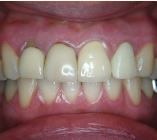

セラミック治療

こんな歯並びでもご心配なく。矯正という方法をとらなくても、ここまできれいに治せるんです。見た目だけでなく歯ブラシもやり易くなりました。笑顔に自信がつきますよ。

- 施術前

- 施術後